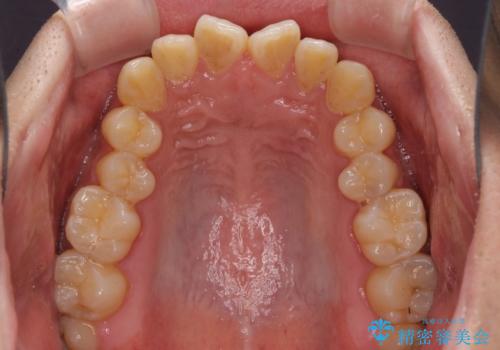

下顎前歯と上顎の部分矯正

- 上下の前歯の叢生を気にして来院された患者様です。

前歯のみの矯正治療を希望でしたが、上顎臼歯が舌側転位していたため、上顎は全体を、下顎は前歯のみを矯正治療することとしました。